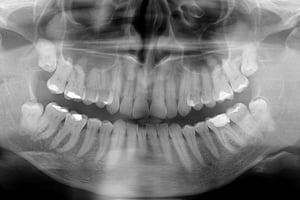

27-latni pacjent zgłosił się do naszej placówki z prośbą o pomoc polegającą na kontynuacji leczenia kanałowego, trwającego już wiele miesięcy. Leczenie przedłużało się z powodu powikłania w postaci złamanego narzędzia endodontycznego, które uniemożliwiało dezynfekcję systemu kanałowego na całej długości. Dodatkową trudnością była lokalizacja narzędzia w połowie długości korzenia za krzywizną kanału, co uniemożliwiało jego widoczność w mikroskopie. Podjęto próbę ominięcia („by passa”) narzędzia, co niestety nie powiodło się. Nieocenioną pomocą w tym precyzyjnym zabiegu okazała się tomografia wolumetryczna, która „sięgała, gdzie wzrok nie sięgał” i ułatwiła bezpieczne usunięcie narzędzia, a następnie pełną dezynfekcję i szczelne wypełnienie systemu korzeniowego. Zabieg trwał 4 godziny (2 wizyty po 2 godziny) i dzięki olbrzymiej cierpliwości pacjenta i precyzji operatora zakończył się sukcesem.